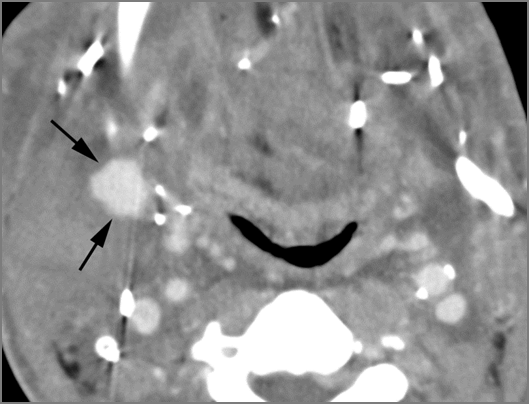

There is reactive cervical lymphadenopathy. |

Yes | NA |

|

If there is suppurative cervical adenopathy the purulent material outside the lymph node(s) capsule(s). |

No | NA |